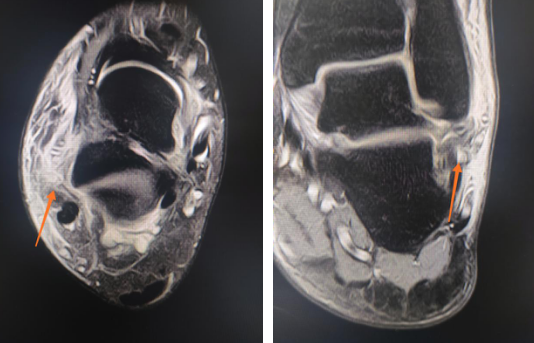

足踝科二病区周祥国医师接诊,给小夏进行了仔细检查,检查结果为右外踝骨折,右外踝关节侧副韧带断裂。

韧带受伤

右外踝骨折